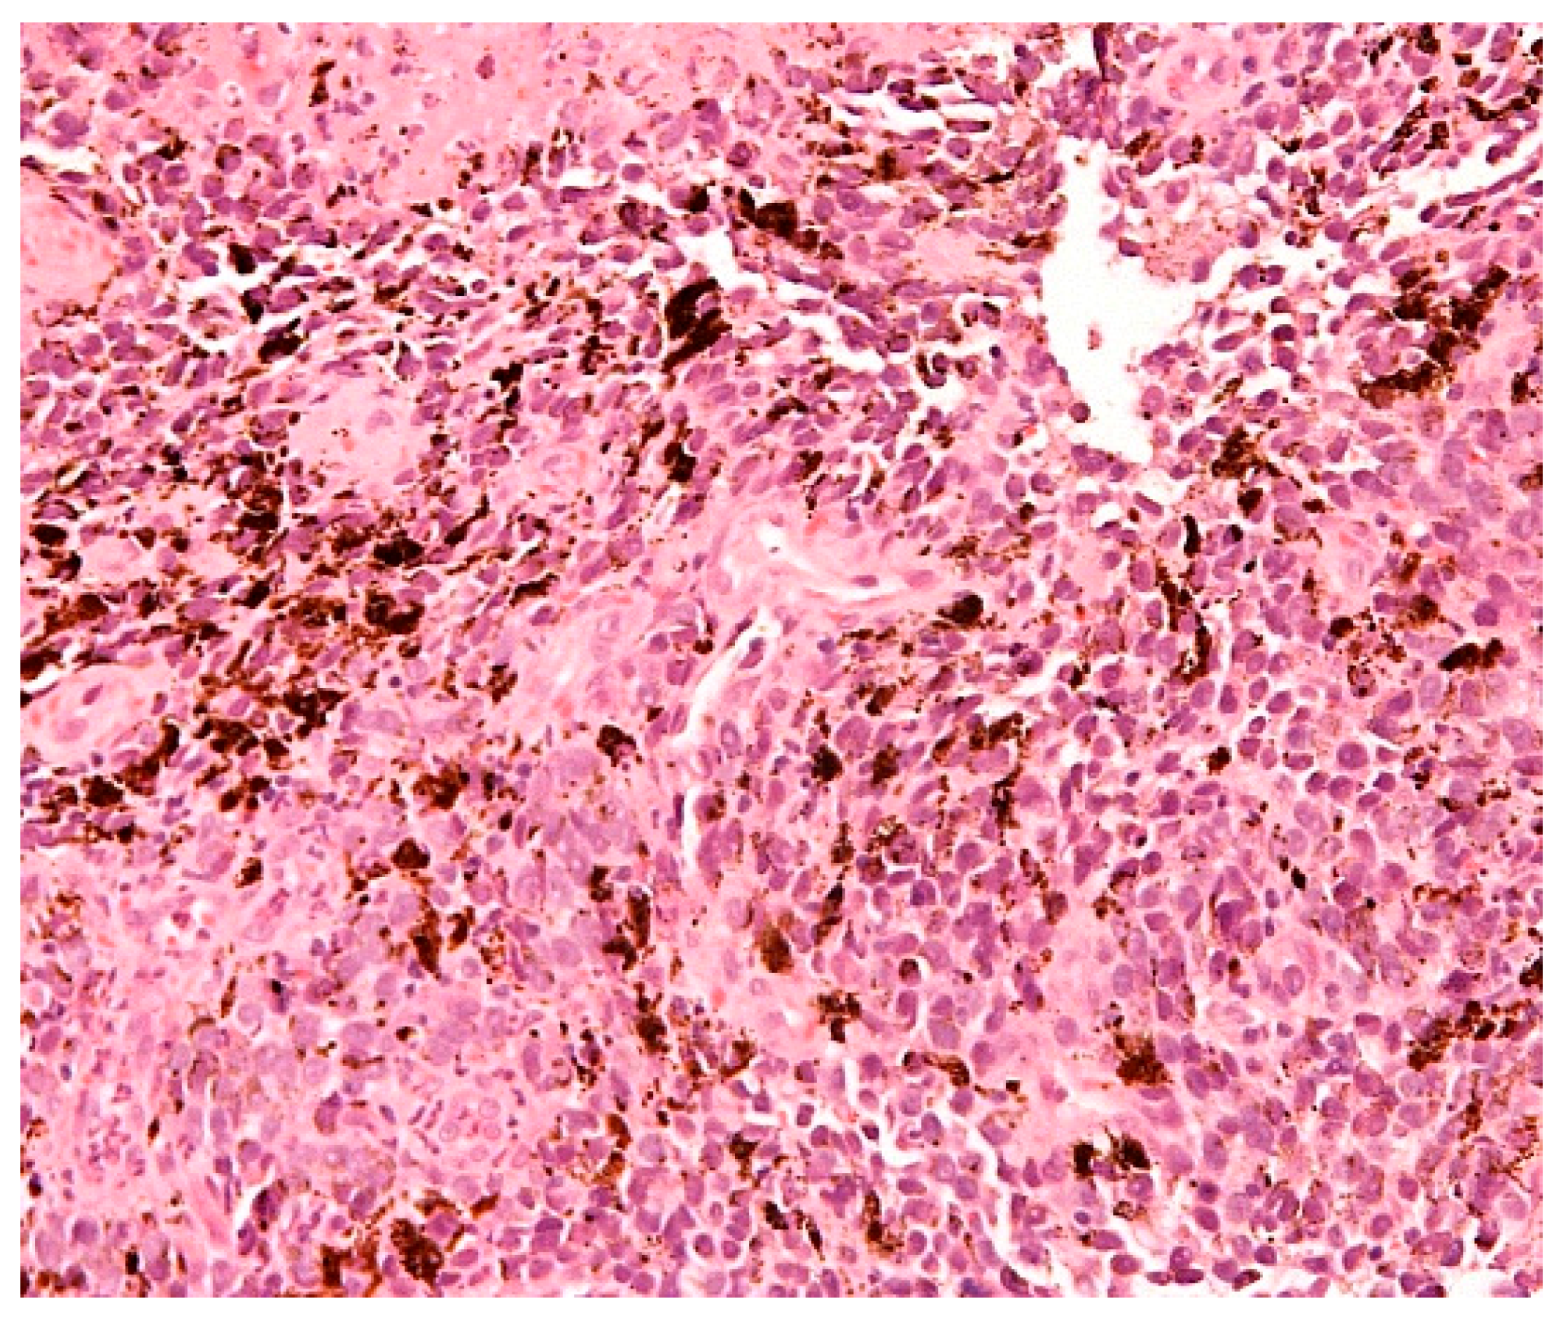

1.4. Diagnosis

1.5. Molecular Characteristics